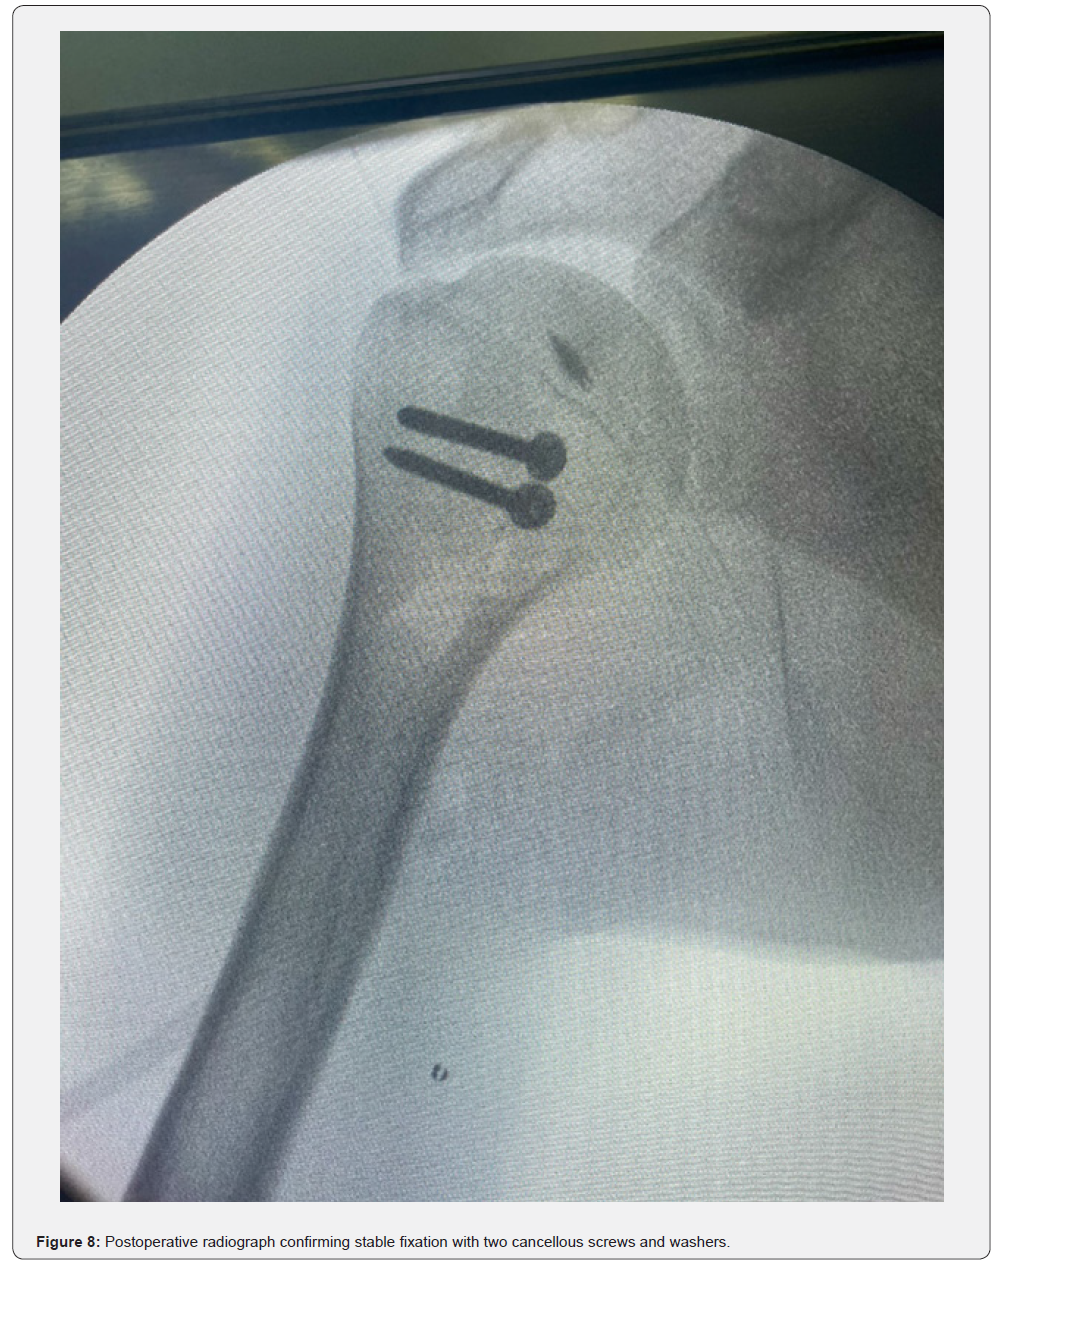

The patient was placed in a beach-chair position under general anesthesia. A standard deltopectoral approach was used. Intraoperatively, the humeral head was found locked posteriorly with fibrous tissue interposition (Figure 4). Open reduction was achieved after careful release of fibrous adhesions and identification of the anterior glenoid defect (Figure 5). The reverse Hill–Sachs defect was managed by a modified McLaughlin procedure: transfer of the subscapularis tendon into the defect using a suture anchor (Figure 6). Fixation was reinforced with two 3.5 mm cancellous screws with washers for stability (Figure 7). Intraoperative fluoroscopy confirmed concentric reduction and stable fixation (Figure 8). External and internal rotation was tested intraoperatively and demonstrated a stable, congruent reduction without evidence of redislocation or subluxation (Figure 9a–9b).

This technique provides stability and allows for biological healing. Defects >40%: Options include humeral head reconstruction with autograft or allograft [11,13,19], rotational osteotomy [10], or shoulder arthroplasty in irreparable cases, particularly in older or low-demand patients [18,22]. Our patient had a ~30% defect, making the modified McLaughlin procedure the most appropriate treatment option. We reinforced fixation with two cancellous screws and washers, ensuring stability. The algorithm concludes with a standardized postoperative rehabilitation protocol emphasizing staged mobilization-from sling immobilization and passive motion to progressive activeassisted and active exercises within 3–6 weeks-to restore stability, range of motion, and functional recovery.